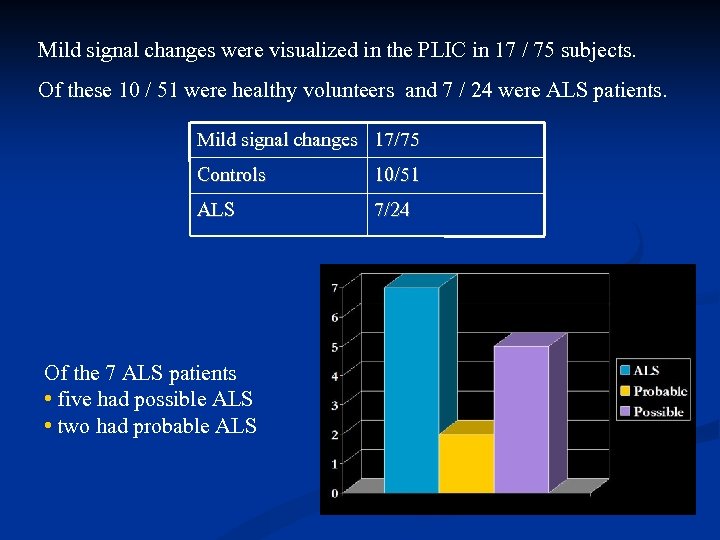

Mild signal changes were visualized in the PLIC in 17 / 75 subjects. Of these 10 / 51 were healthy volunteers and 7 / 24 were ALS patients. Mild signal changes 17/75 Controls 10/51 ALS 7/24 Of the 7 ALS patients • five had possible ALS • two had probable ALS

Mild signal changes were visualized in the PLIC in 17 / 75 subjects. Of these 10 / 51 were healthy volunteers and 7 / 24 were ALS patients. Mild signal changes 17/75 Controls 10/51 ALS 7/24 Of the 7 ALS patients • five had possible ALS • two had probable ALS